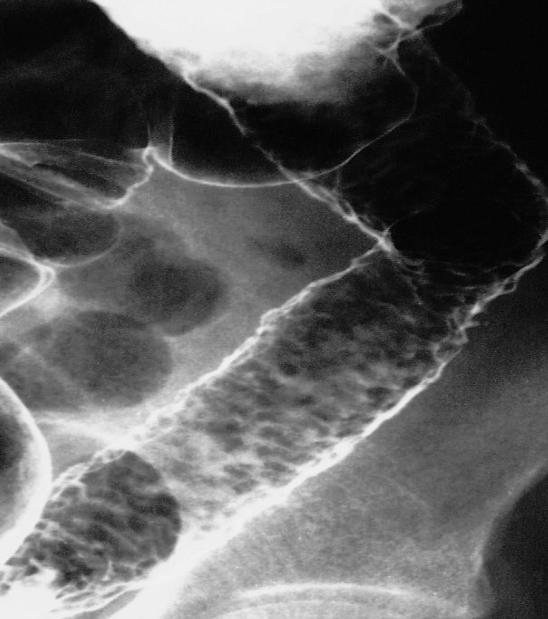

- CROHN’S DISEASE

- Cobble stone appearances